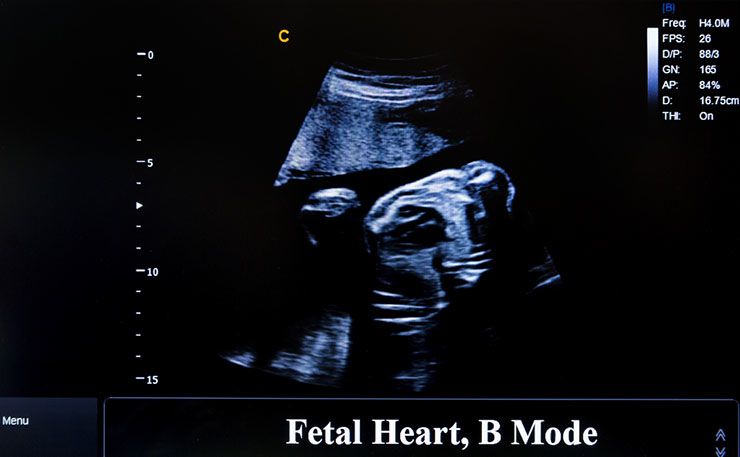

Signs of Labor

“The uterus was contracting regularly and the fetal heart was heard,” the case report explained. While doctors had no idea how the 15-year-old could have possibly gotten pregnant, they were sure that the baby was ready to be born even though there was no vagina for the baby to be born through.

The doctors performed an abdominal exam and they were sure that she had somehow become pregnant. According to the doctors, they could feel the baby was in a head-down position and determined that the intermittent abdominal pains were actually contractions.